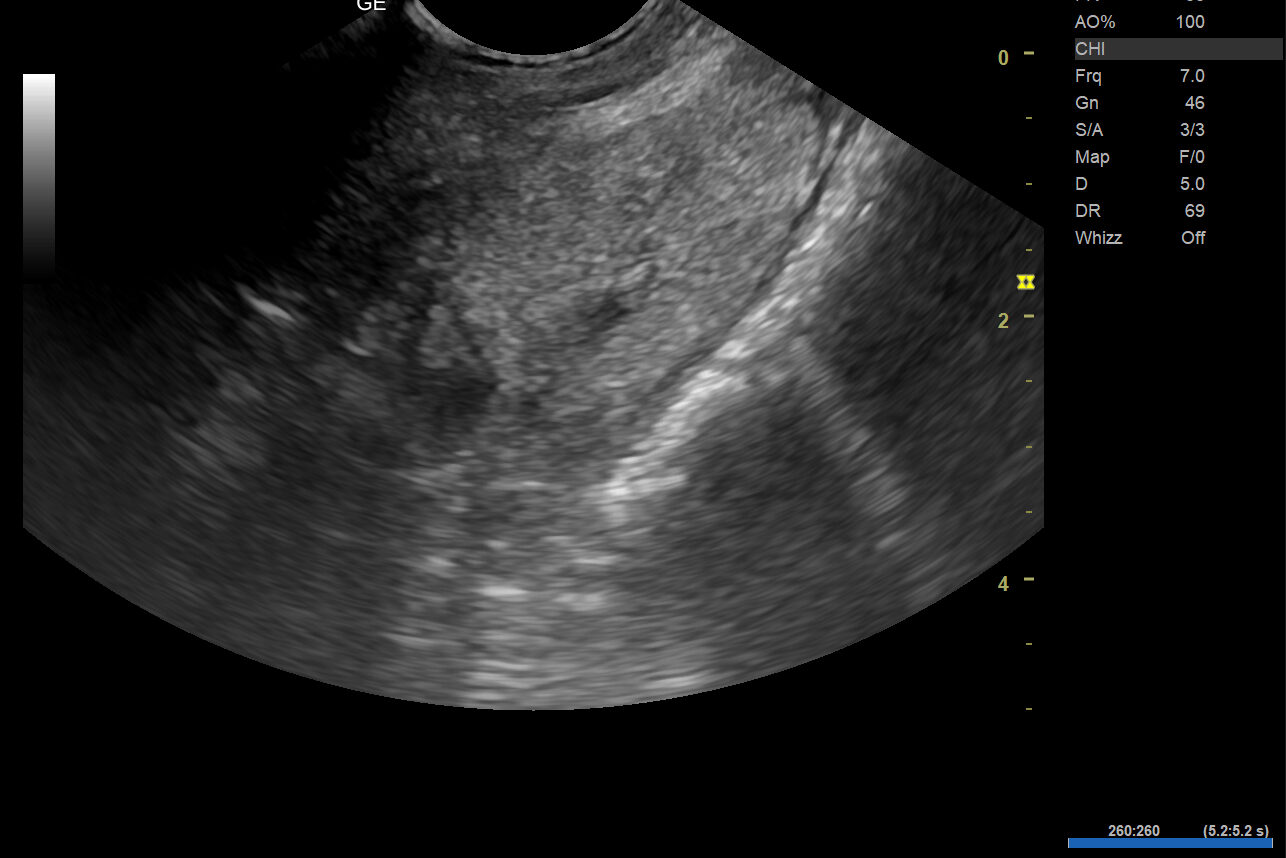

Under utredningen ble det oppdaget at Dino hadde en galleblære fylt med tykt slim, salter og grus. Tilstanden kalles galleblæremukocele. Dette er en alvorlig sykdom der innholdet i galleblæren blir unormalt tykt og hindrer normal tømming.

Ubehandlet kan galleblæren sprekke og føre til bukhinnebetennelse, som er livstruende. Diagnosen stilles ved ultralyd, hvor man ofte ser et karakteristisk mønster inne i galleblæren.